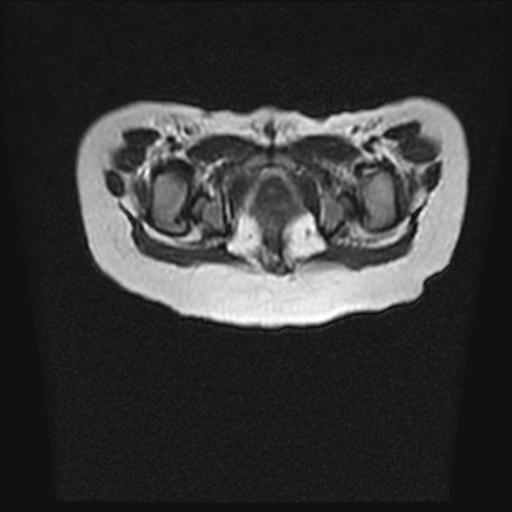

四个月的女婴,ct示脊膜膨出.

脂肪脊髓脊膜膨出

脊柱裂、脊膜膨出